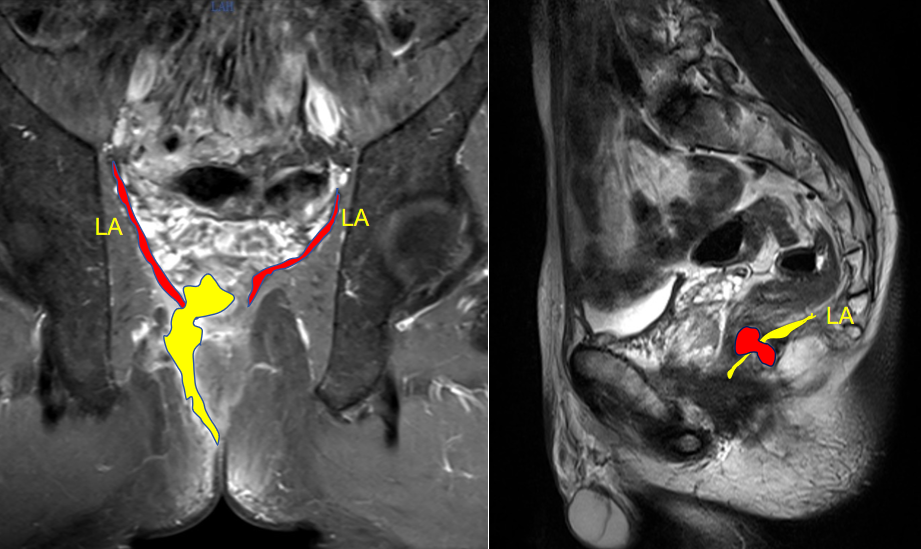

他们先给王先生做了详细的专科检查——王先生的肛周外观看着完全正常,可肛门指检时,能摸到右侧粘膜饱满、压痛,6 时位的肛窦还能触及硬结、压痛。肛周 MRI 更是清晰显示,瘘管主支像 「隧道」一样穿过肛管直肠环,突破肛提肌,并合脓肿形成。最终明确诊断为「高位复杂性肛瘘」。

TROPIS(经肛括约肌间切开术)作为目前一种新兴的肛瘘保留肛门括约肌手术,其核心原理是:①经肛门切开肛门内括约肌,开放内外括约肌间隙,清除感染源。②保留外括约肌,减少对肛门控便的影响。③引流脓腔或瘘管,达到二期愈合。

该术式的核心优势在于:经肛内切开肛门内括约肌,完全敞开括约肌间隙,几乎不损伤肛门外括约肌,极大程度的保护肛门功能和肛周形态。